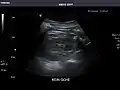

Right kidney

Kidneys: Right and left kidneys measure 11.5 cm and 12 cm in length respectively. No hydronephrosis. Small left lower pole kidney cyst.